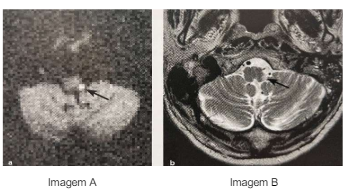

Imagem A: Difusão com restrição na parte dorsolateral esquerda do bulbo Imagem B: T2 com hiperintensidade na parte dorsolateral esquerda do bulbo.

Assinale a alternativa CORRETA que representa a síndrome descrita no caso acima.